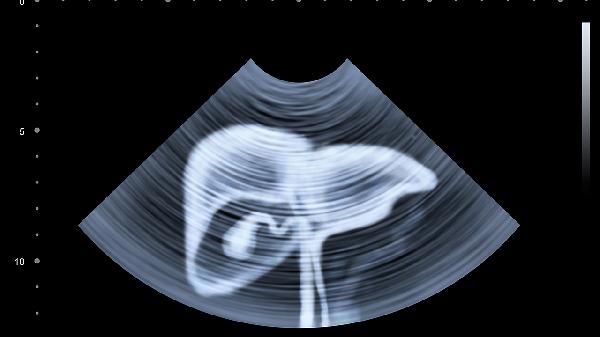

肝癌晚期靶向治疗期间应保持高蛋白低脂饮食,适量补充维生素B族和维生素D。每日记录体重变化及不良反应症状,避免剧烈运动防止病理性骨折。定期复查增强CT或MRI评估疗效,出现持续性发热或严重腹痛需立即就医。靶向药物需在专业肿瘤科医生指导下调整剂量,不可自行停药或更换方案。